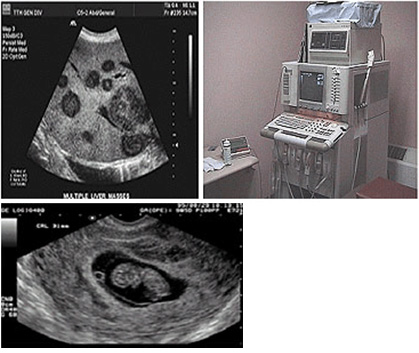

필립스 IU -22는 세계적으로 판매 되는 초음파 장비 중 최상위 모델로 57,000 all digital 채널 및 한 차원 발전된 디지털 beamformer 그리고 supercomputed IPU를 채택하여 매우 뛰어난 영상을 제공하고 영상이 떨어지는 인자를 갖고 있는 부위나 환자인 경우 Tissue Harmonic 기능으로 선명한 영상을 구현하여 정확하고 신속한 진단을 가능하게 합니다.